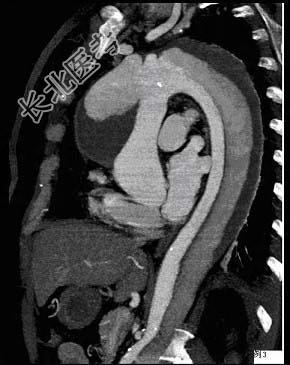

- 多项选择题请看一组主动脉的CT增强图像,正确的描述和结论是 ( )

A、主动脉血栓

B、主动脉瘤

C、主动脉夹层

D、真腔较假腔小

E、真假腔之间线状低密度影为内膜片影